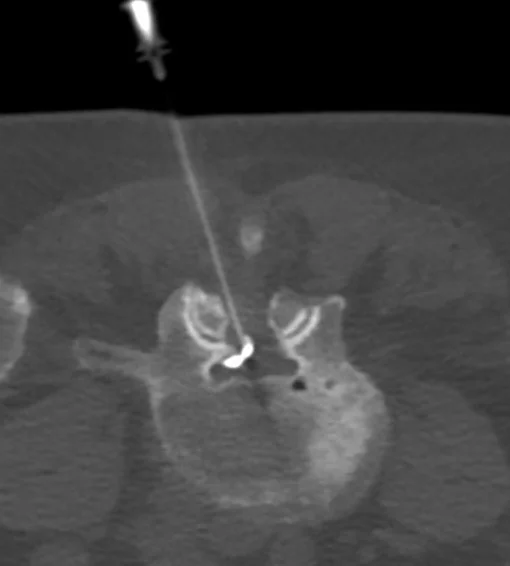

A CT-guided lumbar spine injection is a procedure used to deliver medication directly to the spine to treat pain, inflammation, or nerve irritation in the lower back. This injection can target different areas depending on the condition being treated, including:

Nerve Block: Used to target specific nerves, providing pain relief and helping to pinpoint the source of pain.

Epidural Injection: Aimed at reducing inflammation and pain in the epidural space, often for conditions like herniated discs or sciatica.

Facet Joint Injection: Focuses on the facet joints in the spine, often used to treat arthritis or joint-related pain in the lower back.

Our radiologists take every precaution to minimize these risks by using sterile technique and precise CT imaging guidance throughout the procedure.